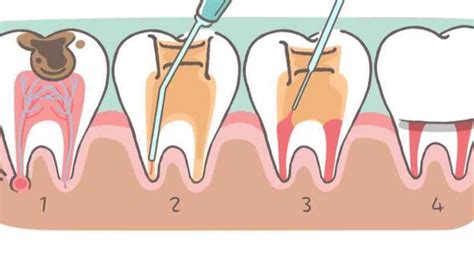

Dažniausiai pasitaikančių dantų traumų rūšys:

Danties vainiko lūžis - nulūžta dalis danties aukščiau dantenų. Lūžis, dėl kurio atsiveria danties pulpa (nervas) yra vadinamas komplikuotu. Jei nulūžo dantis ar jo dalis, pasistenkite ją surasti ir drėgmėje (piene, seilėse, fiziologiniame tirpale, blogiausiu atveju vandenyje) atsinešti pas gydytoją odontologą. Jei lūžio linija bus lygi, o dantis nesutrupėjęs, gydytojas danties vainiko dalį priklijuos atgal. Priklausomai nuo to, kokia jo dalis nuskilo, gali užtekti dantį tik nulyginti arba atstatyti netektą dalį plombuojant. Jei nulūžo pusė ar daugiau danties - reikia surasti nuskilusio danties dalį, įdėti į indelį su seilėmis arba pienu bei atsinešti pas gydytoją odontologą.

Dantų šaknų lūžiai sudaro apie 2-4 procentus pieninių dantų traumų. Jų metu pažeidžiami ne tik kietieji, bet ir pulpos audiniai. Šaknies lūžio metu yra pažeidžiamas danties struktūros vientisumas. Tai reiškia, kad įvykus traumai, kai lūžta šaknis, gali plyšti jungiamieji raiščiai, išjudėti dantis arba skilti danties emalis, gali būti pažeistas vidinis danties audinys - pulpa. Jeigu šaknies lūžis nediagnozuojamas laiku, gali pasireikšti pulpos nekrozė, pakisti danties spalva arba atsirasti vėlyvosios komplikacijos, pavyzdžiui, danties ankilozė (suaugimas su kaulu) ar šaknies rezorbcija (tirpimas).

Patyrus lengvą traumą gydymo gali apskritai neprireikti, pavyzdžiui, maži dantų skilimai, kurie neatveria pulpos, yra šlifuojami, pašalinant aštrius kampus. Jei traumos metu pažeidžiama pulpa, vyksta jos nekrozė, būtinas kanalų valymas. Dantų išnirimai yra vienos pavojingiausių traumų, jų metu gali būti pažeistas alveolinis kaulas, nutrauktas kraujagyslių ir nervų pluoštelis. Pilno išmušimo atveju visuomet įvyksta pulpos nekrozė ir alveolinio kaulo lūžis. Gydytojas odontologas tinkamai paruoš išmuštą dantį ir įstatys į alveolę bei įtvers.